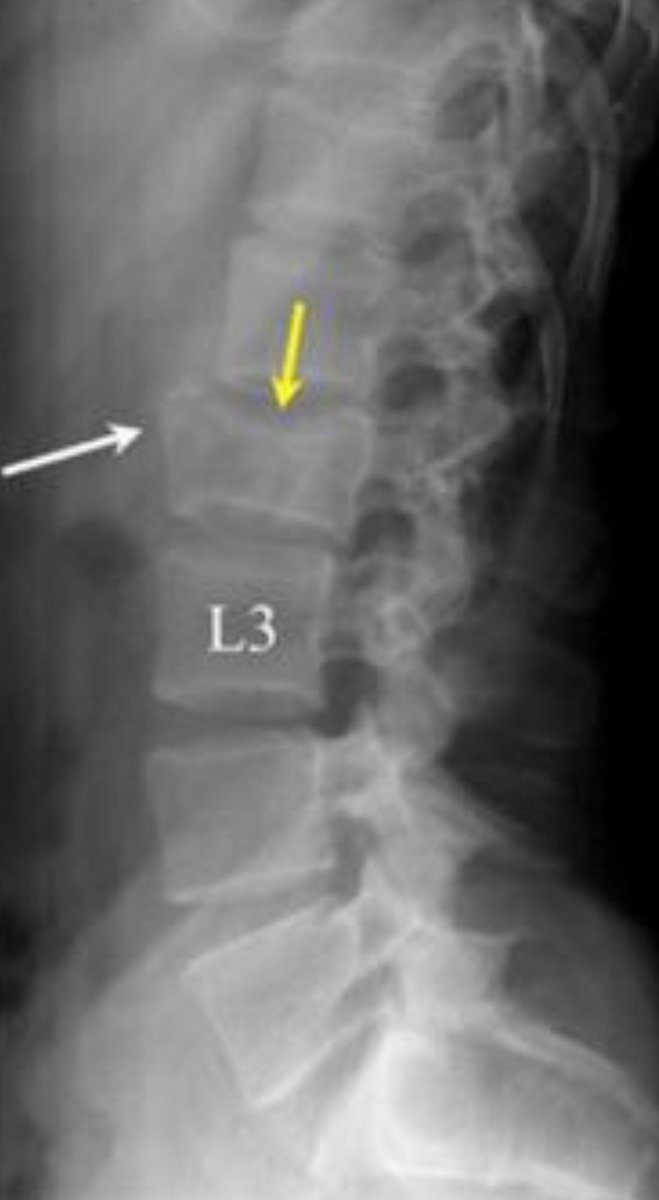

Перелом l2 l3

Перелом l2 l3 111 фото